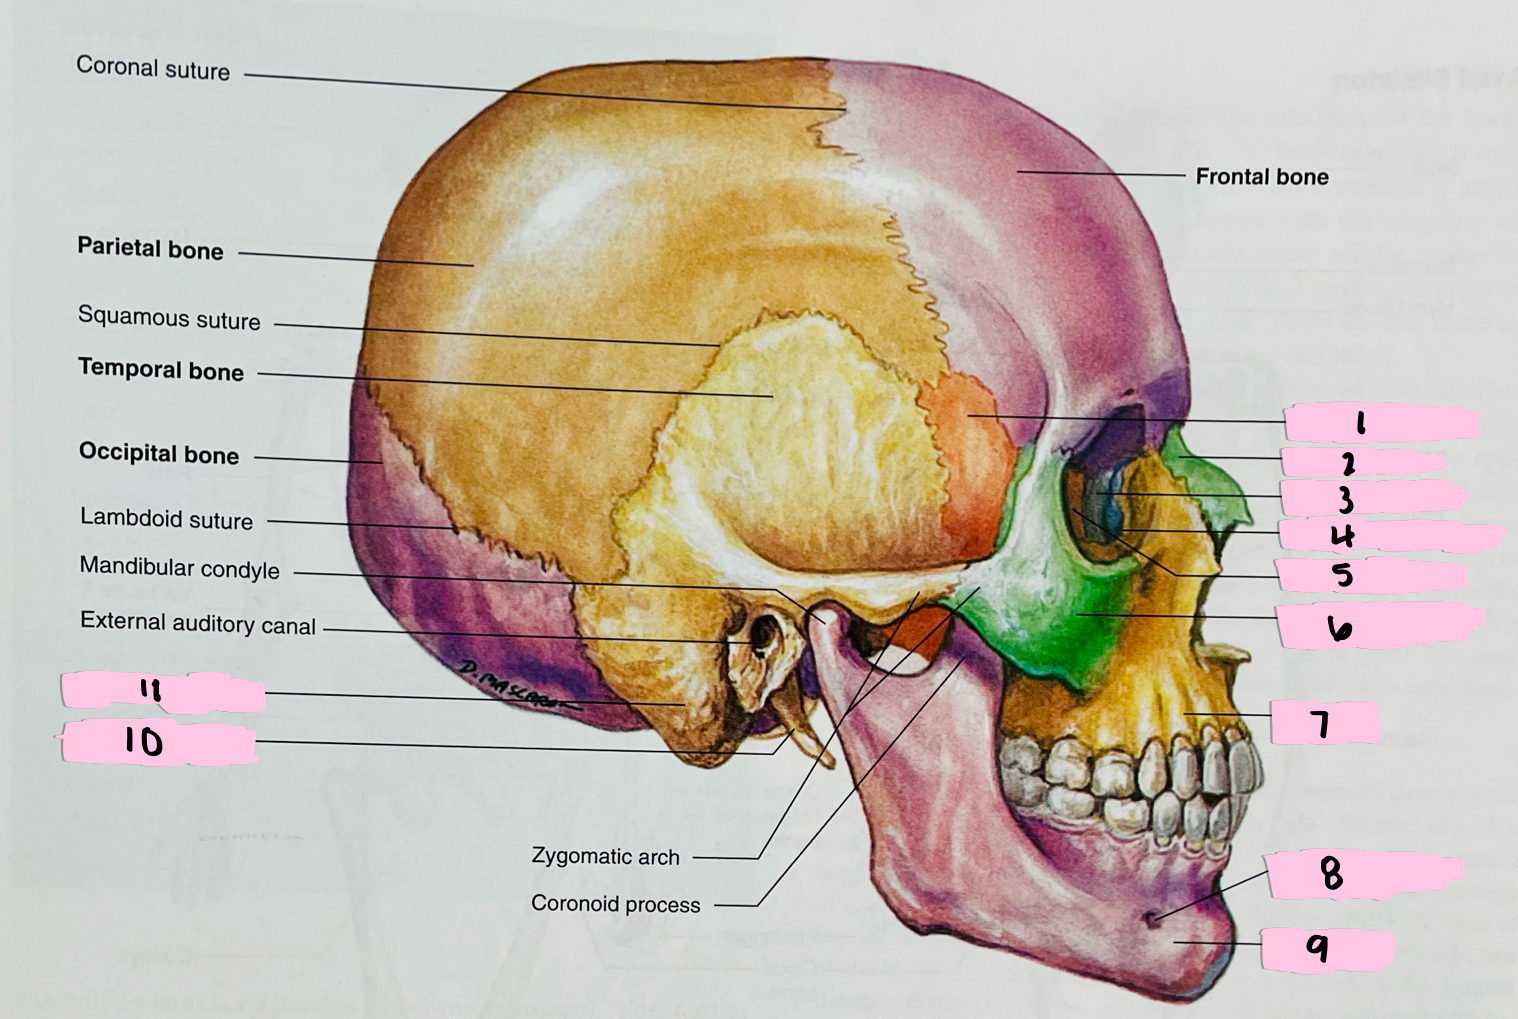

What is 1 pointing to?

Sphenoid bone

What is 2 pointing to?

Nasal bone

What is 3 pointing to?

Lacrimal bone

What is 4 pointing to?

Nasolacrimal canal

What is 5 pointing to?

Ethmoid bone

What is 6 pointing to?

Zygomatic bone

What is 7 pointing to?

Maxilla

What is 8 pointing to?

Mental foramen

What is 9 pointing to?

Mandible

What is 10 pointing to?

Styloid process

What is 11 pointing to?

Mastoid process